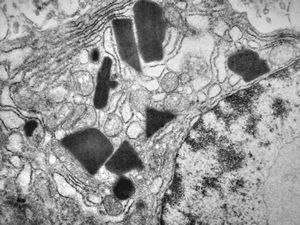

F,21y. | bone marrow - sideroblastic anemia

M,34y. | bone marrow - sideroblastic anemia